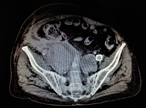

Endovascular intervention for iliac vein thrombosis after simultaneous kidney-pancreas transplant

Meredith Gunder and others

Journal of Surgical Case Reports, Volume 2019, Issue 4, April 2019, rjz024, https://doi.org/10.1093/jscr/rjz024